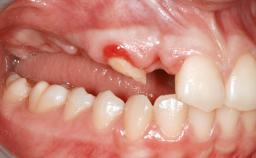

Shell Technique for Horizontal and Vertical Maxillary Bone Augmentation in a Partially Edentulous Patient with Aggressive Periodontal Disease

A 46-year-old woman was referred for treatment whose main complaints were mobility of her fixed partial dentures (right maxilla and left mandible) and periodontal bleeding during function. She also reported having taken systemic antibiotics to treat recurrent swelling in the area of the upper left molars. The patient had not seen a dentist for at least 2 years. She did not smoke and had no history of major systemic disease other than two minor orthopedic procedures some years back. The first-visit examination revealed poor plaque control, tooth mobility, periodontal disease, and a residual dentition widely associated with deep periodontal pockets.

Infection at Implant Site None Chronic Acute

Soft Tissue Anatomy Intact Defective

Bone Volume Horizontally and vertically sufficient Horizontally deficient Deficient vertically or deficient vertically AND horizontally